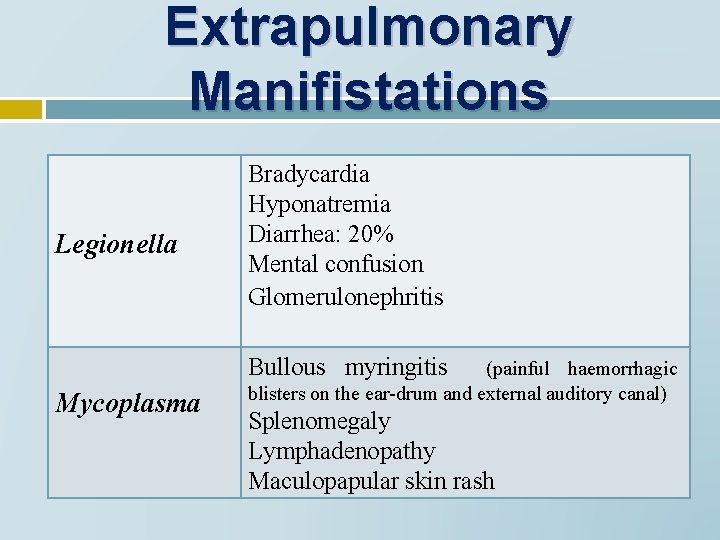

Extrapulmonary Manifistations Legionella Bradycardia Hyponatremia Diarrhea: 20% Mental confusion Glomerulonephritis Bullous myringitis Mycoplasma (painful haemorrhagic blisters on the ear-drum and external auditory canal) Splenomegaly Lymphadenopathy Maculopapular skin rash